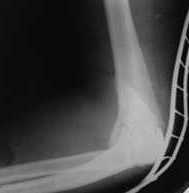

Подскажите пожалуйста, как можно в дальнейшем этому больному помочь. В марте первая операция, пришлось оперировать на 16 сутки в виду инфицированных садин и анемии. Заживление первичным натяжением,раняя разработка после операции, а через 2 нед болевой синдром,и постепенно движения в локтевом суставе ограничились до полного анкилоза. Повторно через 4 месяца вторая операция" артролиз,удаление оссификатов, удаление фиксаторов, реостеосинтез этой же реконструкционной пластиной и винтом" интраоперационно после удаления оссификатов и фиксаторов обнаружил, что перелом не сросшиеся, поэтому пришлось синтезировать заново. Зажило рана первично, объем движений в локтевом суставе сгибание 70, разгибание160, ротационные движения востановились полностью,вроде бы успокоились. Опять постепенно в течении 8 нед после повторной операции постепенно движения ограничились до 80 - 110, на снимке оссификат. Снимки во вложении, буду рад Вашим советам. Спасибо!